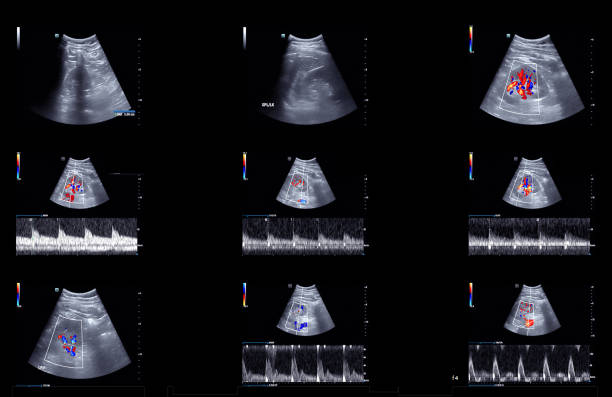

경동맥 초음파 검사로 알수있는병 - 검사 결과 해석

검사 결과를 해석할 때, 의사는 다음 사항을 고려합니다.

- 경동맥의 크기와 형태: 경동맥이 충분히 넓고 매끄럽게 유지되는지 확인합니다.

- 혈류 속도: 혈액이 경동맥을 흐르는 속도를 측정하여 혈액순환에 이상이 없는지 확인합니다.

- 혈액 응고물질의 존재: 콜레스테롤과 혈액 응고물질이 경동맥 벽에 쌓여 있는지 확인합니다.